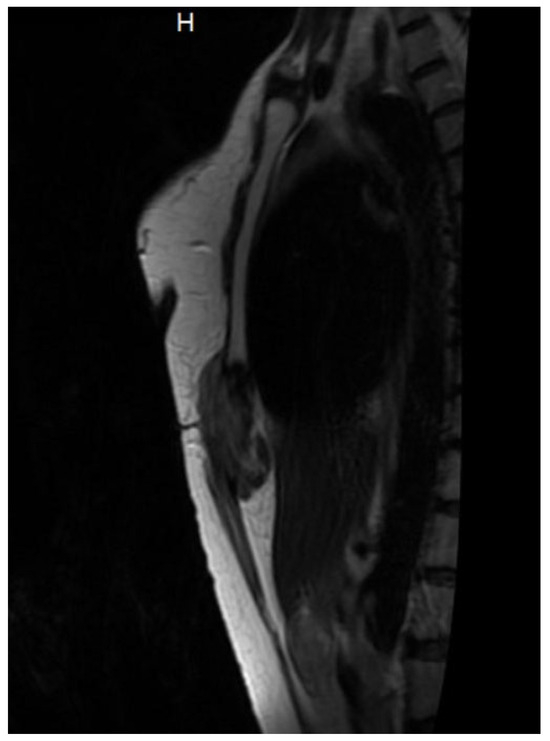

3.1. Diagnosis and Imaging Characteristics